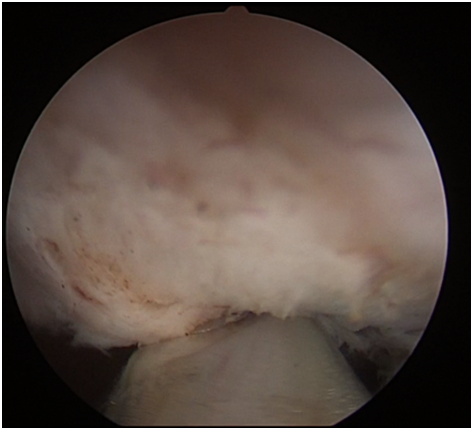

剜除后的效果

無體表切口的經(jīng)尿道前列腺切除術(shù)是前列腺增生手術(shù)治療的“金標(biāo)準(zhǔn)”。激光和等離子切除速度快、止血效果好,已成為前列腺增生微創(chuàng)治療的主要術(shù)式。在此基礎(chǔ)上基于精準(zhǔn)解剖的“剝橘式”經(jīng)尿道前列腺激光或等離子剜除術(shù),可以將微創(chuàng)手術(shù)效果發(fā)揮至極致。1470nm激光經(jīng)尿道前列腺手術(shù)正具有此優(yōu)勢。該激光手術(shù)具有切除前列腺組織徹底、創(chuàng)面平整、出血少、術(shù)后恢復(fù)快、手術(shù)風(fēng)險小、療效更持久等優(yōu)點,可以明顯減少尿失禁等并發(fā)癥,并且最大程度留取了前列腺標(biāo)本,是前列腺增生最先進(jìn)的腔內(nèi)治療手段,尤其適合高齡患者。目前已成為國內(nèi)外大體積前列腺增生的首選微創(chuàng)治療手段。